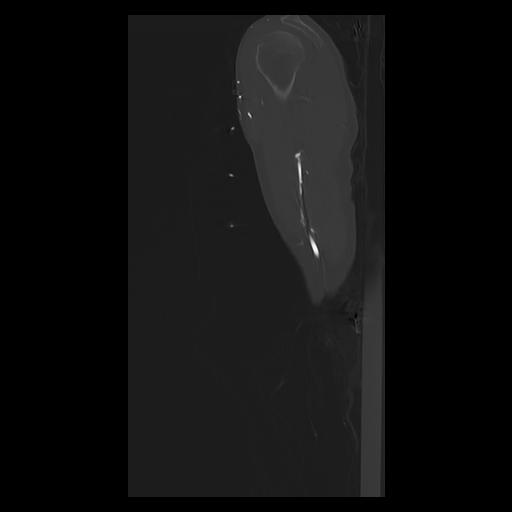

33 PULMON,CE,Sagittal,3.000,PULMON,Sagittal,